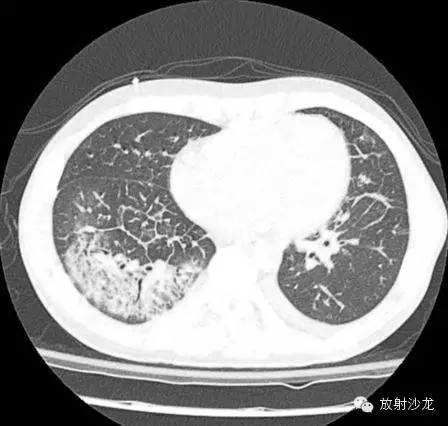

两周后CT:

(第一次胸片示两肺中野及右肺下野多发斑片状高密度影。胸部CT示多发斑片状磨玻璃样密度增高影以及实变影,同时伴有小叶间隔的增厚。其中有些病灶部分表现为“铺路石征”。两周后CT随访显示这些病灶的密度和范围都增大。电视辅助胸腔镜肺活检下,活检标本病理诊断结果为急性纤维素性机化性肺炎。上述病变经高剂量糖皮质激素治疗三周后明显改善。)